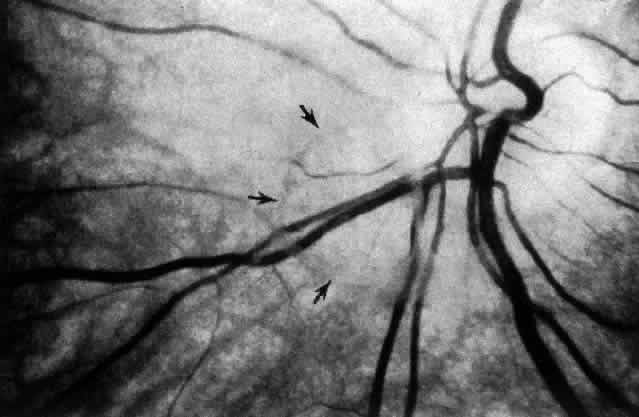

Fig. 13. Posterior vitreous in the left eye of a 59-year-old man. The vitreous cortex (white arrows) envelopes the corpus vitreous and contains multiple, small, highly refractile points that scatter light intensely, which are cells known as hyalocytes. There is a “hole” (black arrows) in the prepapillary posterior vitreous cortex through which vitreous extrudes into the retrocortical space. Larger amounts of vitreous extrude through the premacular vitreous cortex, and fibers course from the central vitreous into the retrocortical space. (Sebag J, Balazs EA: Human vitreous fibres and vitreoretinal disease. Trans Ophthalmol Soc UK 104:123, 1985)

Fig. 14. The posterior vitreous is detached, and the prepapillary hole in the posterior vitreous cortex (arrows) can be seen anterior to the optic disc (slightly below and to the left of the optic disc) (Sebag J: The Vitreous--Structure, Function and Pathobiology. New York, Springer-Verlag, 1989)

Fig. 15. Anomalous posterior vitreous detachment. Vitreous can remain attached to the macula even in the presence of posterior vitreous detachment. In such cases, vitreous can extrude through the premacular vitreous cortex and fibers can insert into the macula. B, C, and D are an artist's rendition of this phenomenon. A demonstrates actual vitreous extrusion into the retrocortical space in a postmortem human specimen (see Fig. 4D) (B and C adapted from Jaffe NS: The Vitreous in Clinical Ophthalmology. St. Louis, CV Mosby, 1969; D adapted from Jaffe NS: Vitreous traction at the posterior pole of the fundus due to alterations in the posterior vitreous. Trans Am Acad Ophthalmol Otolaryngol 71:642, 1967)